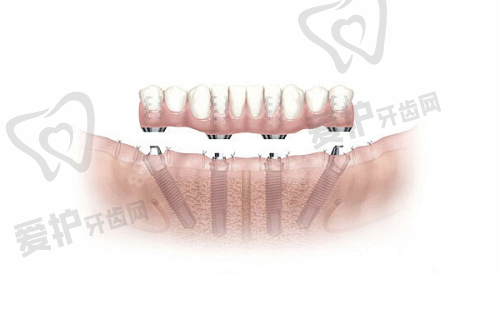

2024年有不同的价格情况。2024年8月28日消息显示,武汉仁爱口腔单颗种植牙价格1840元起一颗,半口种植牙费用1.3万元起,全口种植牙价格3.9万元起,all - on - 6全口种植牙费用在3.9万 - 6万元起。相比于武汉多家口腔机构,武汉仁爱口腔种植牙价格都属于中等偏下的,但是其做种植牙品质并不大折扣。